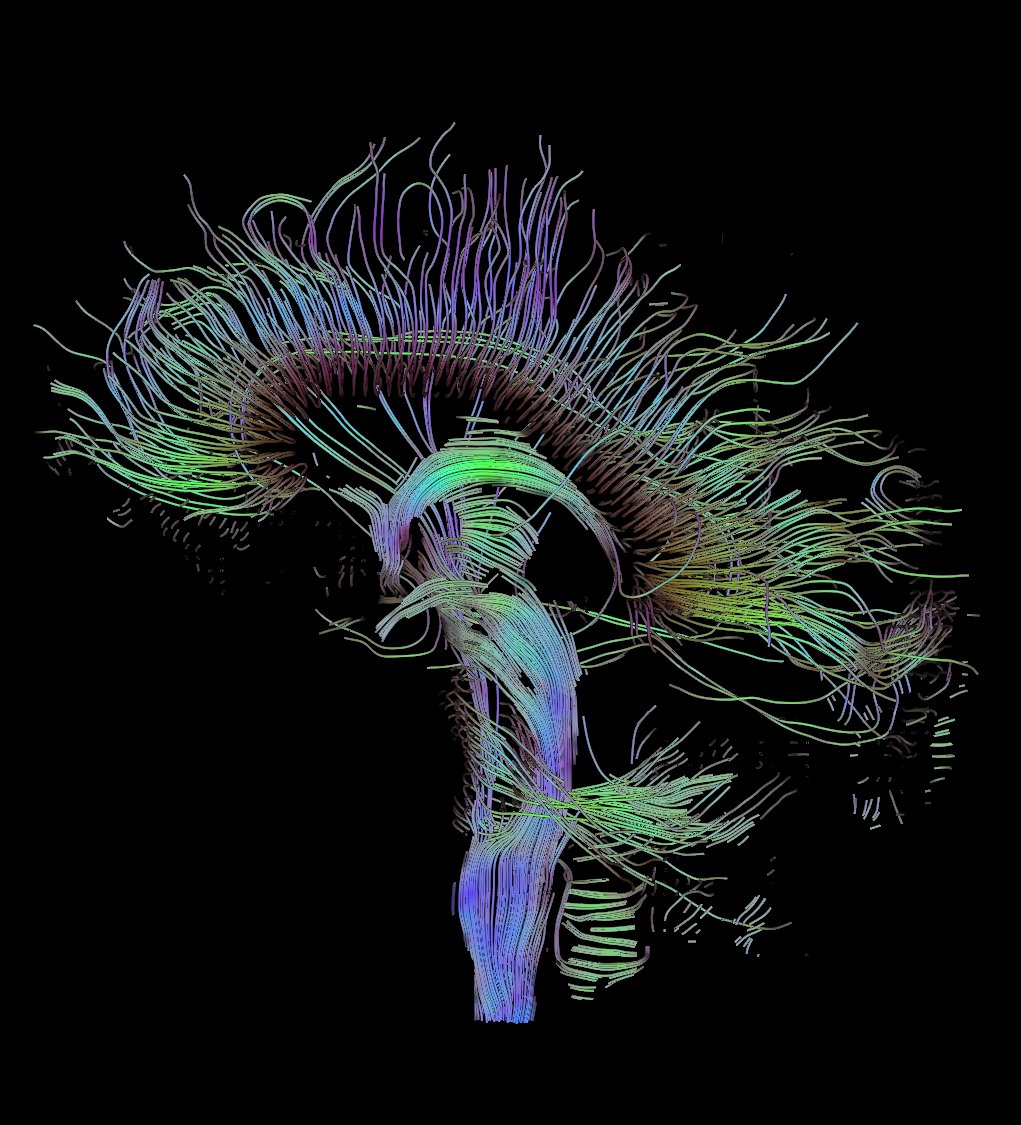

La sustancia blanca del cerebro es el conjunto de fibras neuronales que conectan las diferentes regiones del cerebro y desempeña un importante papel en la inteligencia. Se encuentra situada debajo de la materia gris externa. Se compone de haces de cables, o axones, que conectan billones de neuronas y llevan señales eléctricas entre ellos.

Mapas 3D del cerebro

Los científicos utilizaron una técnica particular de la imagen por resonancia magnética (IRM) que permite observar el cerebro de una persona en directo, así como dibujar los caminos de los axones. A continuación, los ordenadores convertían los escáneres cerebrales en mapas 3D del cerebro.

La sustancia blanca del cerebro es el conjunto de fibras neuronales que conectan las diferentes regiones del cerebro y desempeña un importante papel en la inteligencia. Se encuentra situada debajo de la materia gris externa. Se compone de haces de cables, o axones, que conectan billones de neuronas y llevan señales eléctricas entre ellos.

Mapas 3D del cerebro

Los científicos utilizaron una técnica particular de la imagen por resonancia magnética (IRM) que permite observar el cerebro de una persona en directo, así como dibujar los caminos de los axones. A continuación, los ordenadores convertían los escáneres cerebrales en mapas 3D del cerebro.